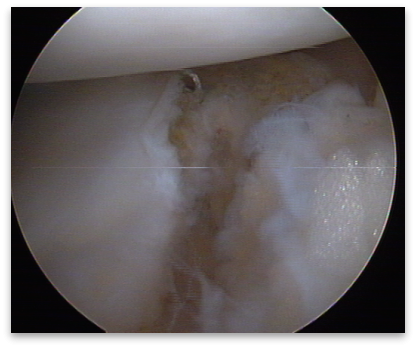

1)首先关节镜检查,评估半月板撕裂位置、长度、撕裂类型。对于不适合缝合的半月板组织进行清理;

2)使用刨削刀和半月板锉处理半月板撕裂缘,进行新鲜化;

4)将半月板双针穿入缝合套管。先穿刺半月板上表面,将缝合针穿过半月板、关节囊并穿出体外。将另一针穿入缝合套管,跨过半月板撕裂缘并刺穿半月板完成一次垂直褥式缝合(图5)。根据撕裂缘长度以5mm间距完成接下来的半月板缝合;